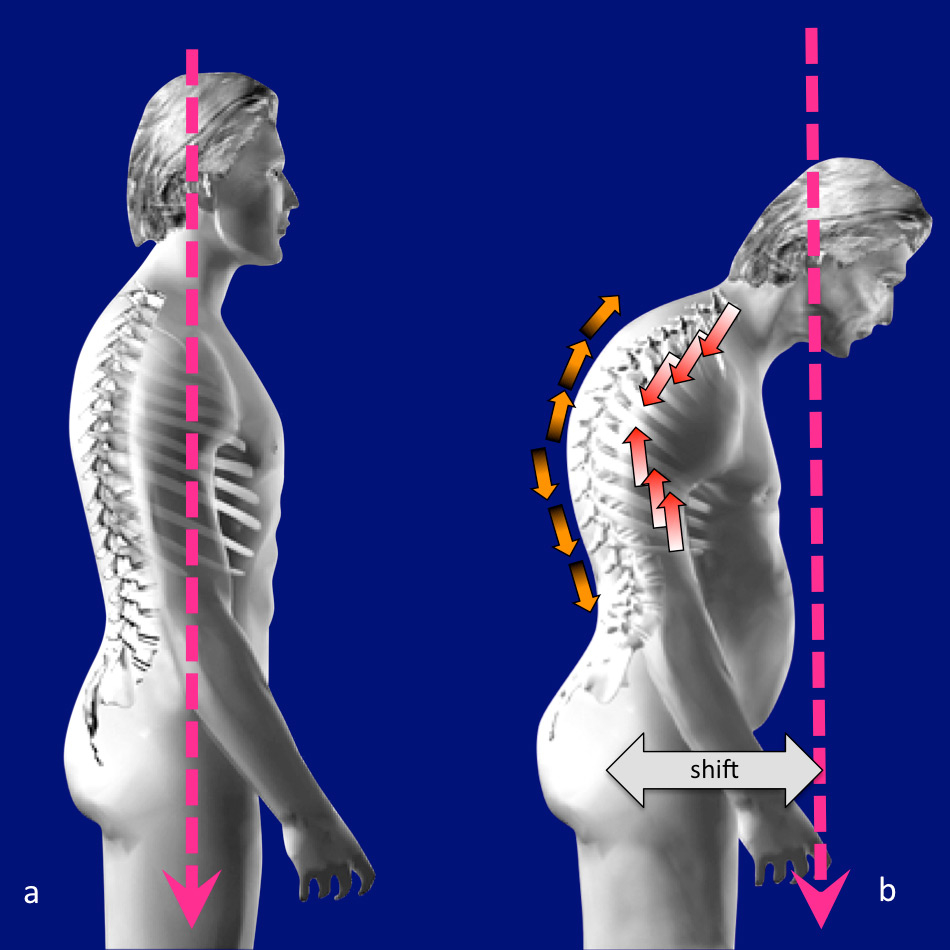

Vertebral body compression fractures (VBCF) are the hallmark of osteoporosis, and its incidence increases exponentially with increasing age [1]. In general VBCF are considered to be benign, but epidemiological data show major morbidity and loss of quality of life comparable to that of hip fractures. Mortality in patients with VBCF is higher than in a non fractured population. [2, 3]. These fractures frequently result in loss of physiological posture, which in turn leads to higher loads on the vertebrae on the one hand and higher stress for the back muscles on the other. (fig. 1)

Figure 1

Loss of posture due to vertebral factures: The centre of gravity (pink) is in line with the hip joint in a balanced spine (a). Due to vertebral fractures increased kyphosis occurs and the centre of gravity is shifting forward, throwing the spine out of balance (b). This leads to higher compression loads on the vertebrae (red arrows) and higher strain on the back muscles (orange arrows).